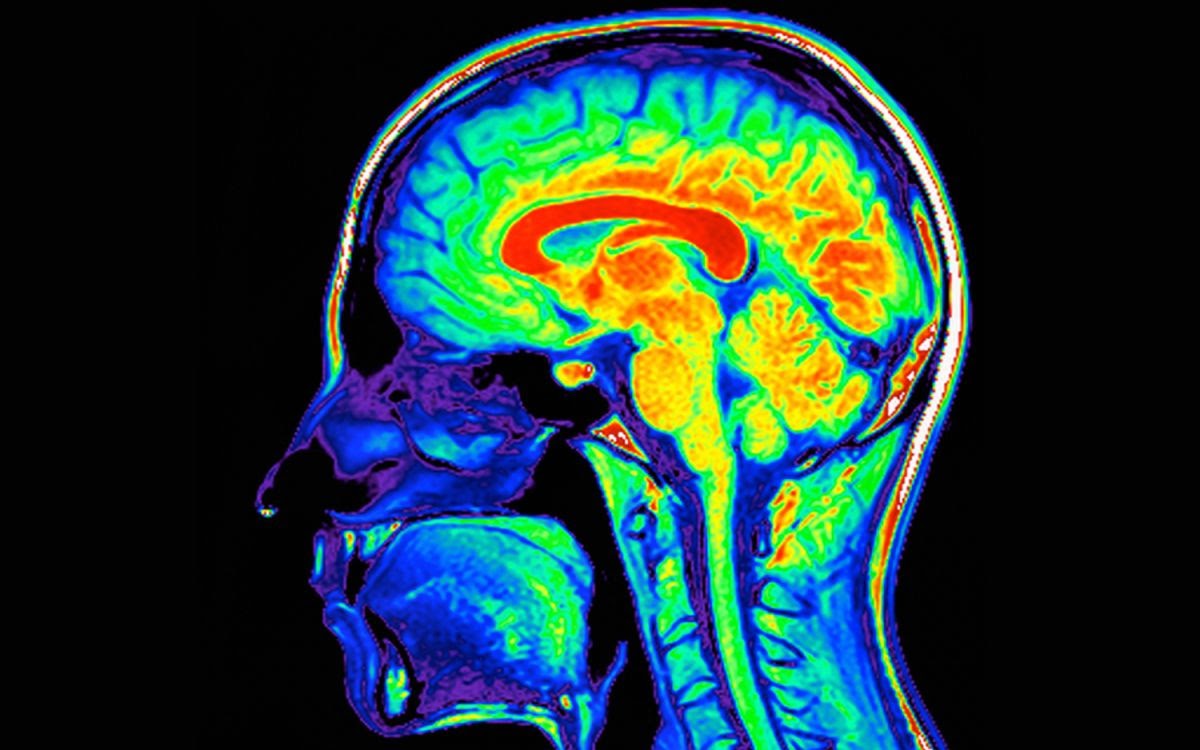

Dr. Libell told us only a movement disorders specialist could issue a definite Parkinson’s diagnosis. The nearest specialist to us was at Cabell Huntington Hospital in Huntington, West Virginia, a facility about three hours away. We made the appointment and went for a consultation with Dr. Suresh G. Kumar. In order to confirm a Parkinson’s diagnosis, Greg would need to undergo a DaT scan, a day-long outpatient procedure that involves a chemical injected into a vein and destined for the brain, which is imaged using single photo emission computerized tomography, or SPECT scanning. The scan produces an image of the brain lit up with primary colors: red, yellow, blue. Greg underwent a DaT scan in early 2020, just before the Covid pandemic began. The test confirmed that Greg had Parkinson’s, his brain a map of colors as bright as a kindergartner’s drawing.